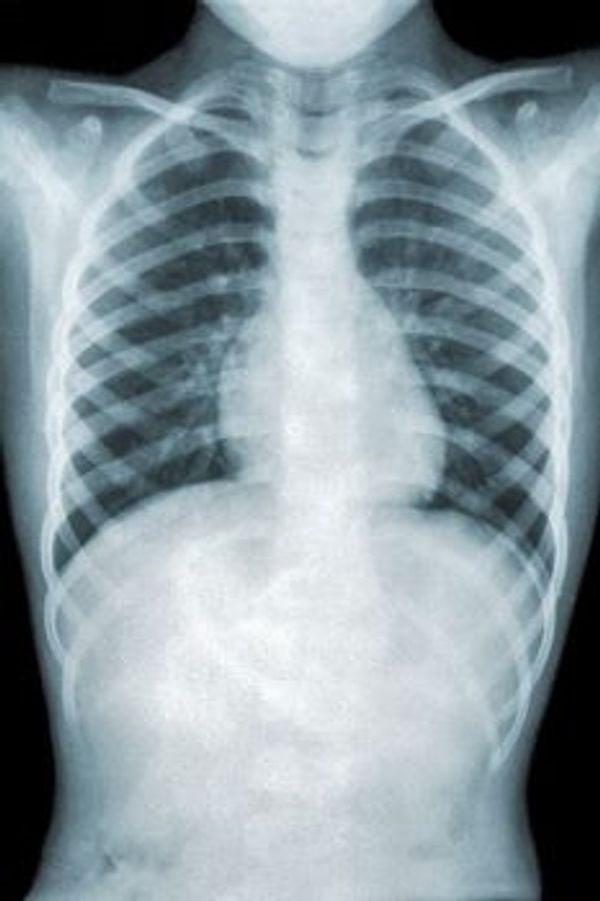

Over het algemeen veroorzaakt de mycoplasma pneumoniae een mild verlopend griepachtig beeld, met veel hoesten en een lichte malaise. Meestal heeft iemand geen koorts, maar soms treden er wel spier- en hoofdpijn op. De verschijnselen ontstaan in de meeste gevallen geleidelijk in meerdere dagen tot een week. Dit in tegenstelling tot bijvoorbeeld influenza (griep) waarvan de verschijnselen vaak heel acuut optreden. De incubatietijd kan variëren van één tot drie weken. Soms verloopt de infectie echter ernstig en ontwikkelt deze zich tot een longontsteking met langdurige hoest. Deze longontsteking wordt ook wel een atypische longontsteking genoemd, wat zoveel wil zeggen als dat de uitingsvorm ervan afwijkt van een ‘normale’ longontsteking. Daarnaast kun je, als je besmet bent geweest met deze bacterie, op een later tijdstip opnieuw een infectie ermee doormaken.